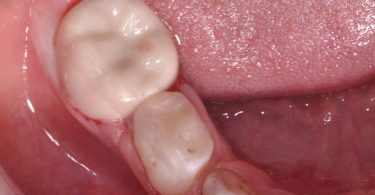

Foi realizado um exame clínico e radiológico inicial (fig. 1 a 3), tendo sido diagnosticada, entre outras lesões de cárie, uma lesão de cárie profunda com atingimento pulpar no segundo molar temporário inferior direito (fig. 3). Foi proposta a realização de uma pulpotomia com agregado trióxido mineral (MTA) e a colocação de uma coroa pré-formada. As várias possibilidades restauradoras foram apresentadas e discutidas com os pais, que decidiram optar pela colocação de uma coroa pré-formada de zircónia, por motivos estéticos.